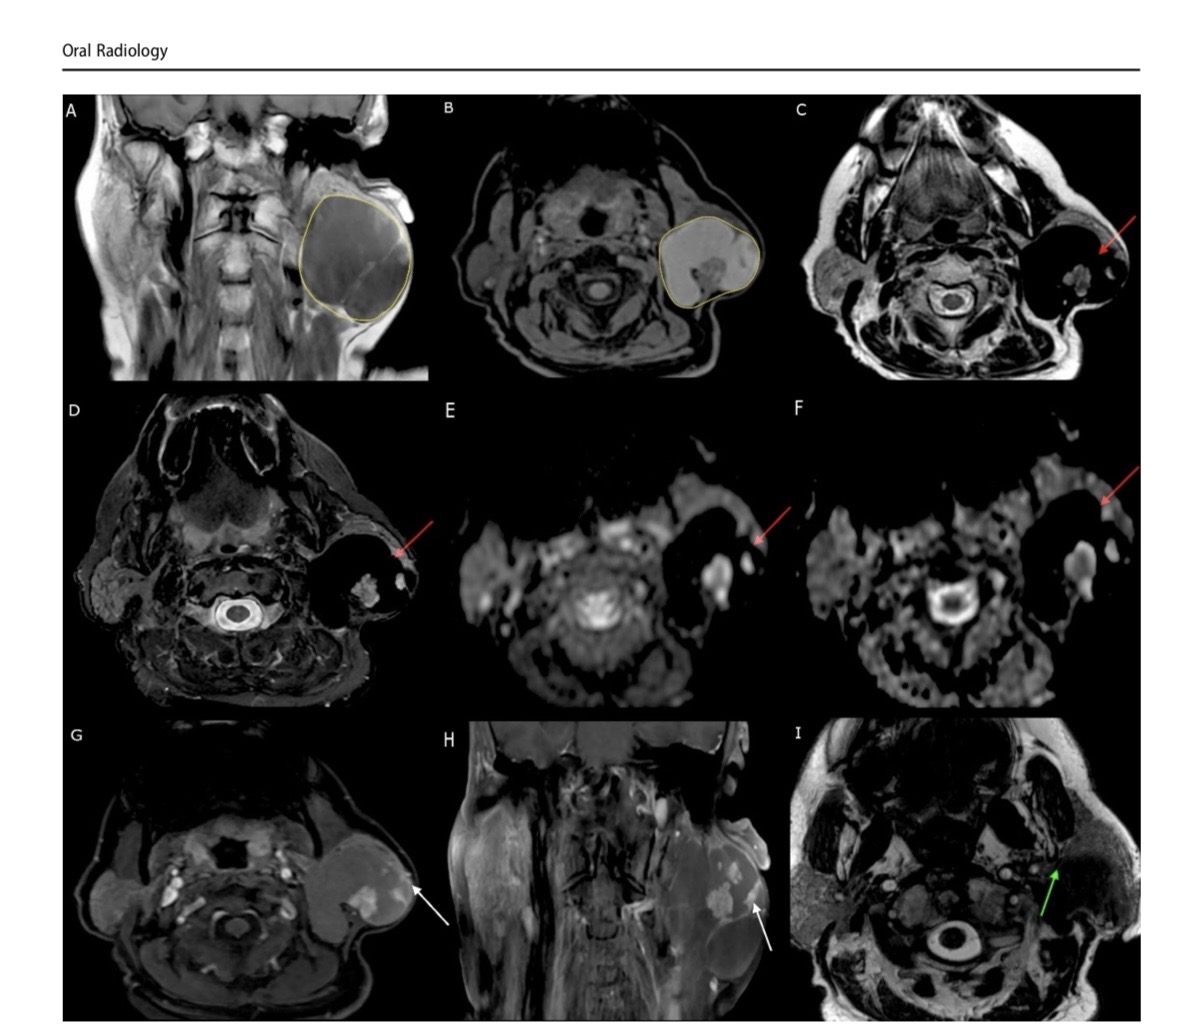

Авторите описват за първи път специфични образни находки при този тип тумор, установени чрез мултипараметрична магнитнорезонансна томография (MRI). Според специалистите този образен модел може да подпомогне по-точната предоперативна диагностика на подобни редки образувания и да улесни планирането на хирургичното лечение.

Образните изследвания - компютърна томография и мултипараметрична магнитнорезонансна томография разкриват характерни особености на тумора. На MRI се установява специфична комбинация от находки: силно понижен сигнал на определени последователности („signal void"), повишен сигнал на T1-претеглени изображения и минимално контрастно усилване на кистозните части на лезията, като усилване се наблюдава основно в папиларните структури. При двата случая е установено изместване, но не и инфилтрация на лицевия нерв - ключова информация за безопасното хирургично лечение.